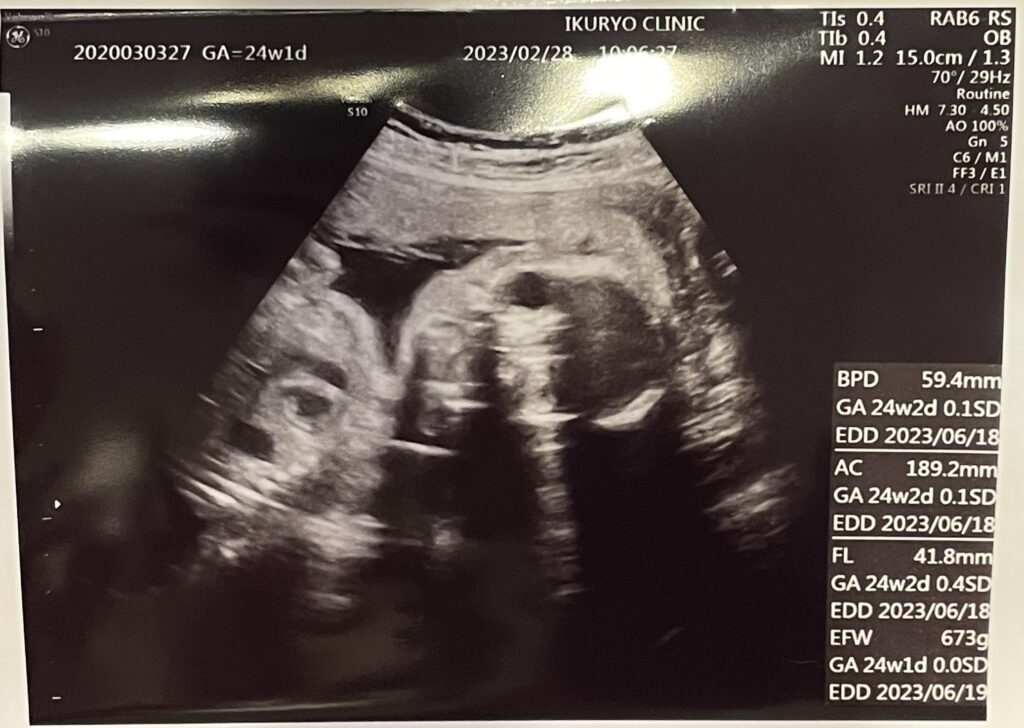

6回目の妊婦健診の内容はこんな感じでした。

- 経腹エコー(4D)

- 血液検査

経腹エコー(4D)

今回の産院はオプションではなく、基本で4Dエコーがついていることに毎回驚きます。

妊娠中期の血液検査として、妊娠24週の妊婦健診の時に血液検査をします。

血液検査の内容は、こんな感じ。

- 貧血検査

- 血糖検査